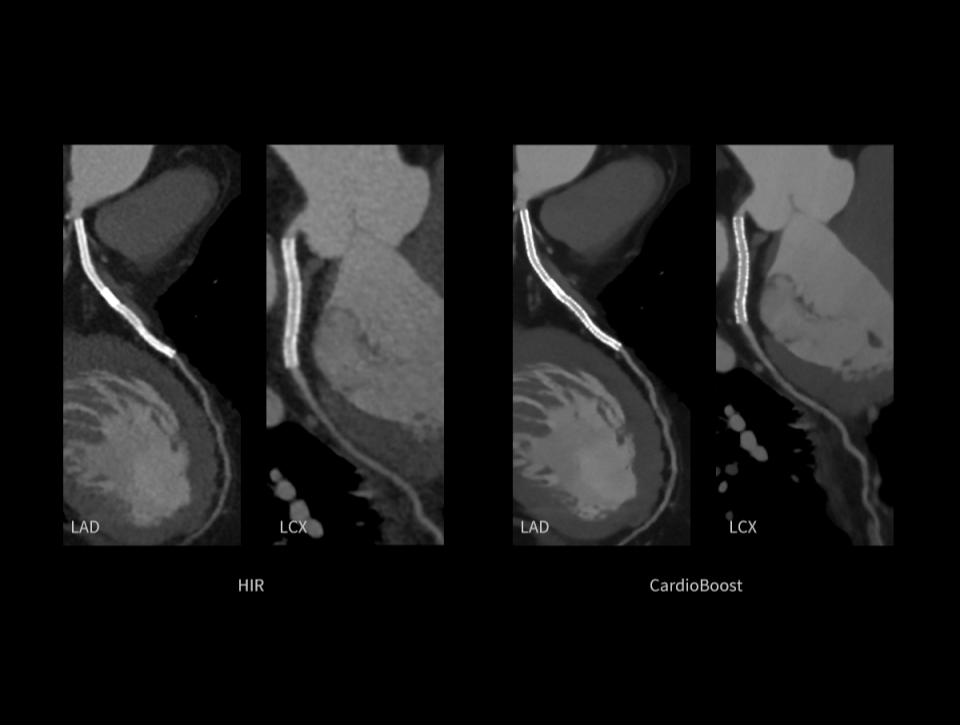

CardioBoost

Algoritm de reconstrucție bazat pe inteligență artificială, special conceput pentru imagistica cardiacă, care oferă o rezoluție spațială excepțională și capacitate avansată de suprimare a artefactelor.

Reducerea zgomotului imaginii, oferind o vizualizare mai clară a arterelor coronare și îmbunătățirea contrastului în interiorul vaselor cu stent.

Îmbunătățirea delimitării contururilor plăcilor, cu o diferențiere mai clară între plăcile dure și cele moi.

Îmbunătățirea afișării arterelor coronare și reducerea artefactelor de mișcare prin algoritmi AI.